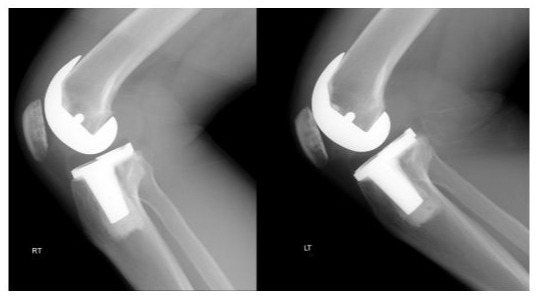

Radiographs of the knees of a 67-year-old woman who had osteoarthritis in both knees (Figure 2A-B).

Figure 2A: Standing anteroposterior radiograph of both knees taken 4 years after surgery, showing that the NexGen LPS-Flex prostheses are embedded solidly in a satisfactory position. There are no radiolucent lines and there is no osteolysis around the components in either knee.

Figure 2B: Lateral radiograph showing that NexGen LPS-Flex prostheses are fixed satisfactorily. There are no radiolucent lines and there is no osteolysis around the components in either knee.

The radiographic results were similar in the NexGen LS-Flex and Freedom TKA groups with regard to the alignment of the knee and the position of the femoral and tibial components in the coronal and sagittal planes. If one assumes a tolerance level of 3°, then the prevalence of outliers ranged from 2 to 4% for all parameters in the NexGen LPS-Flex TKA group and from 1 to 3% in the Freedom TKA group. These differences between the groups were not significant (P > 0.05; Table 4). No knee in either group had osteolysis around the components (Figures 2 and 3).